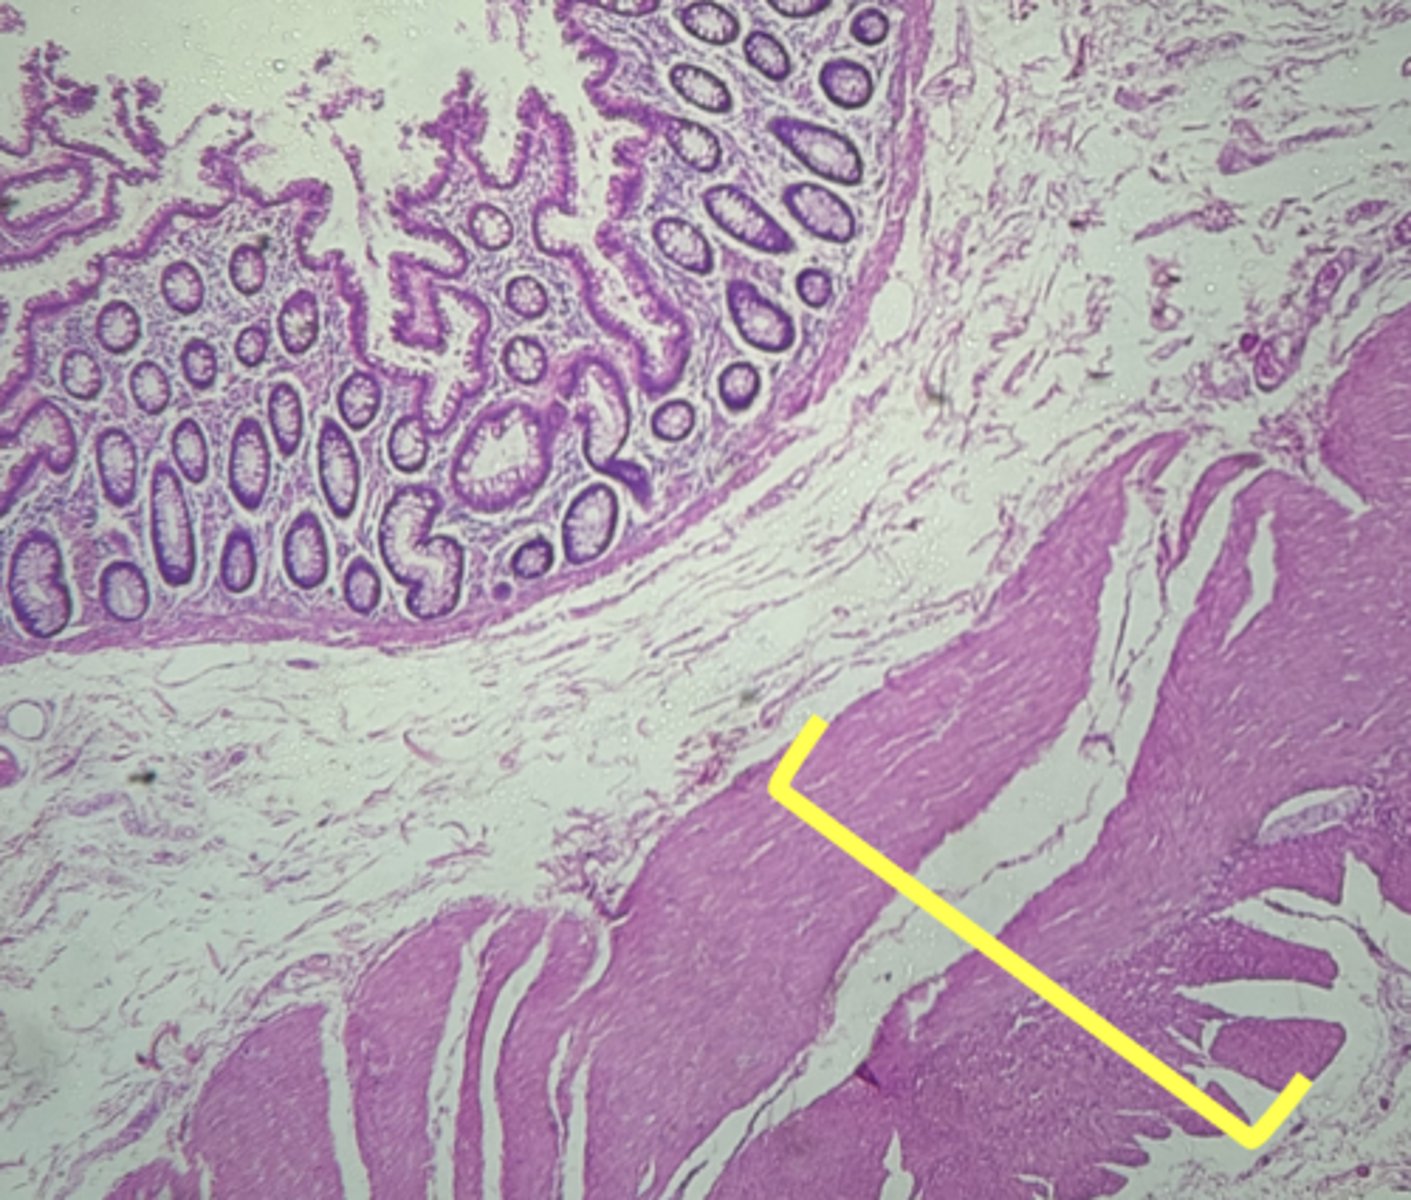

Duodenum (small intestine-cross section)

name the tissue

mucosa

(duodenum)

myscularis externa

Submucosa

Brunner's glands (KEY CHARACTERISTIC)

circular layer

longitudinal layer

Villi (KEY CHARACTERISTIC)

simple columnar epithelium

type of cell

intestinal crypts

lamina propria

muscularis mucosa